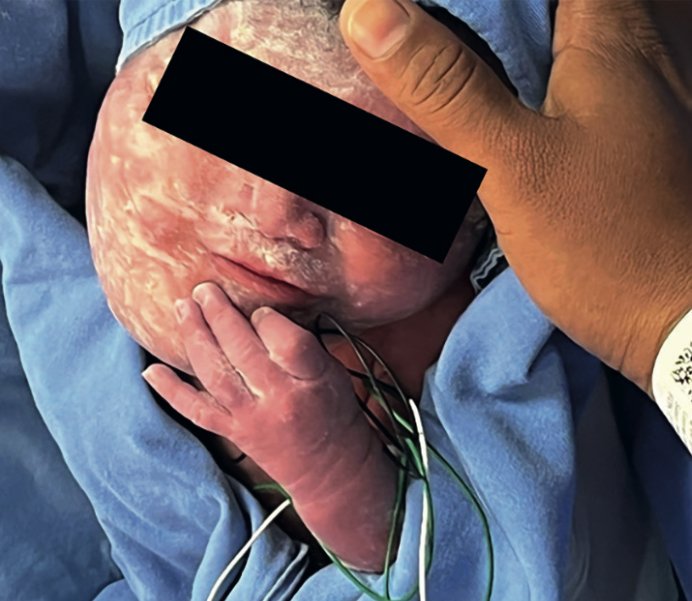

<strong>Figura 3</strong>

Figura 3. Recién nacido con lesión en el hemicuello derecho. En la resonancia magnética se advirtió una lesión multiquística que afectaba el piso de la boca, con extensión a la hipofaringe y mediastino.